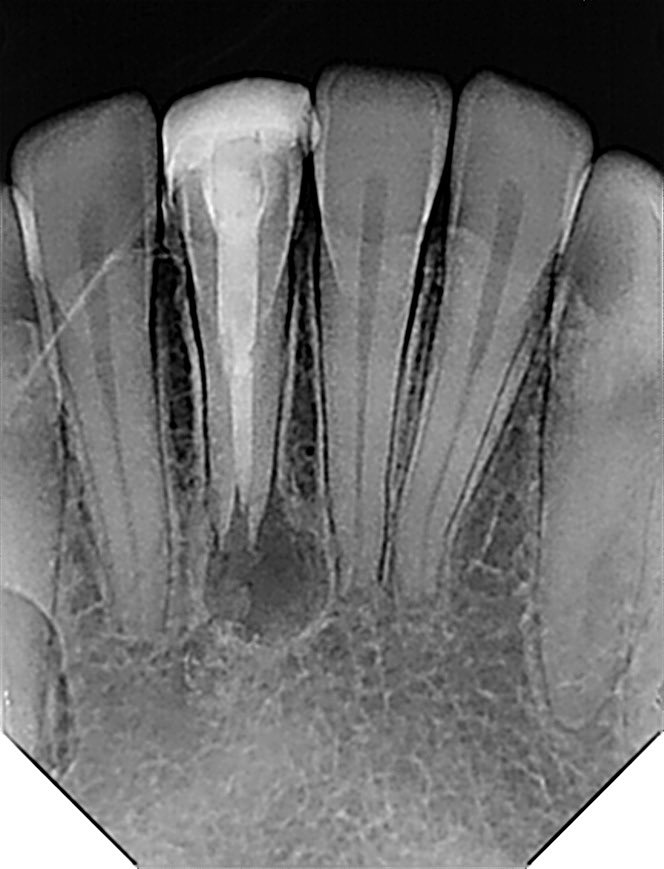

طبيب مقيم في علاج الجذور و عصب الأسنان 🦷 🦷 Endodontic resident at @ksmcmedia 📍Riyadh